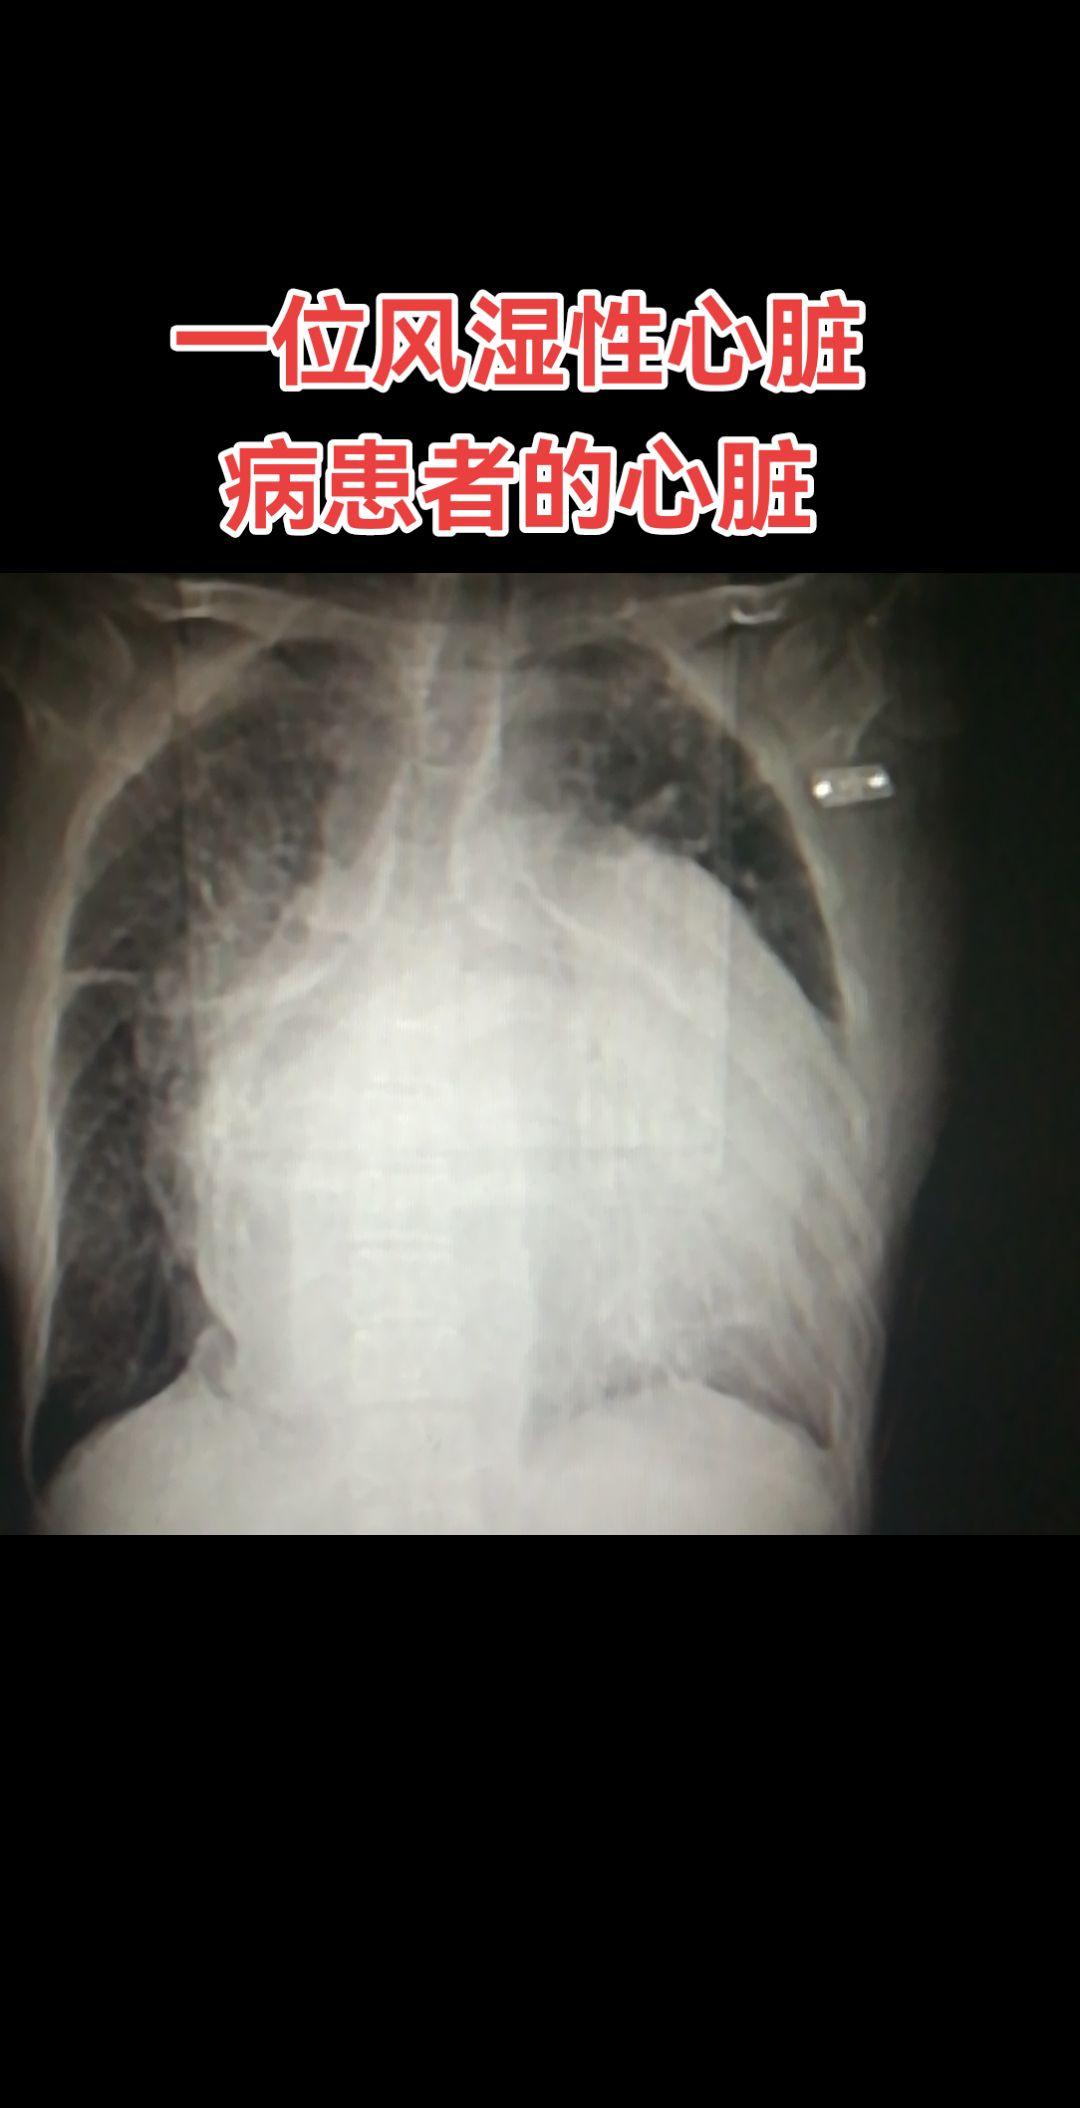

医学影像 日常分享 健康 原创视频 每天跟我涨知识